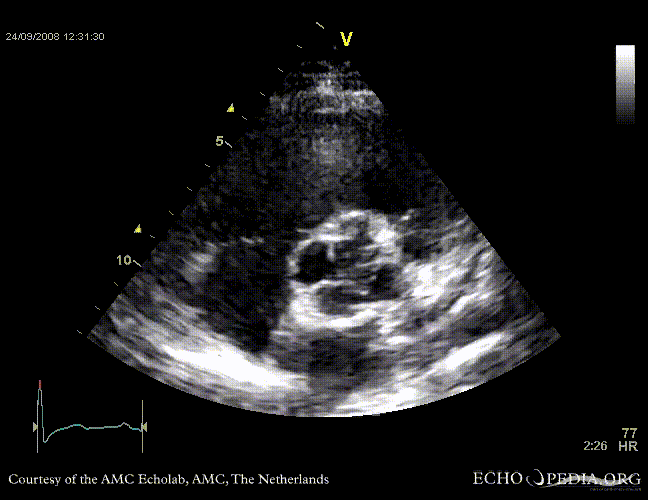

PSAX through aortic valve, clearly showing four valve leaflets PSAX through aortic valve, clearly showing four valve leaflets